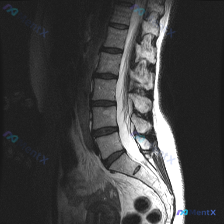

整理到一份影像资料,情况有点意思: - 关注点是“脊柱侧弯”,但只提供了腰椎MRI T2序列矢状位图像 - 矢状位里能看到的是:腰椎生理前凸变直,多节段椎间盘T2信号普遍减低(L4/5、L5/S1尤其明显),L4/5、L5/S1椎间盘有突出/膨出,后缘轮廓不平整,高度也有变窄 - 另外还能看到硬膜囊...

整理了一份影像读片的病例材料,先抛出来大家一起讨论: - 影像来源:腰椎MRI(T2序列,矢状位) - 核心影像表现: 1. L2/L3、L3/L4、L4/L5椎间盘T2低信号(黑盘征),L5/S1信号也有减低;L4/L5、L5/S1椎间隙略窄,伴椎间盘向后弥漫膨出,硬膜囊前缘受压、变形,相应节段椎...